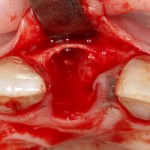

После удаления зуба и сопутствующей гранулемы, остается большая по размеру лунка с тонкой и поврежденной воспалительным процессом вестибулярной стенкой:

Первым делом, необходимо определиться с подготовкой лунки под имплантат. Проверить правильность позиционирования лунки можно с помощью аналогов имплантов, входящих в комплект XiVE Dentsply Implants:

Напомню, что при правильном позиционировании импланта в области фронтальных зубов, он прилегает к небной стенке лунки, а его ось выходит на небную поверхность будущей коронки. В крайнем случае, на режущий край.

Имплантат по объему всегда меньше, чем сам зуб:

Поэтому у нас возникает вопрос заполнения «пустого» пространства между вестибулярной стенкой лунки и поверхностью импланта. И, как ни странно, с Bio-Oss Collagen это удобнее сделать до установки имплантата.

Графт адаптируется (с помощью скальпеля), устанавливается в нужное положение. Для этого, опять же, очень удобно использовать аналоги имплантов из имплантологического набора (в крайнем случае, остеотомы или пины параллельности):